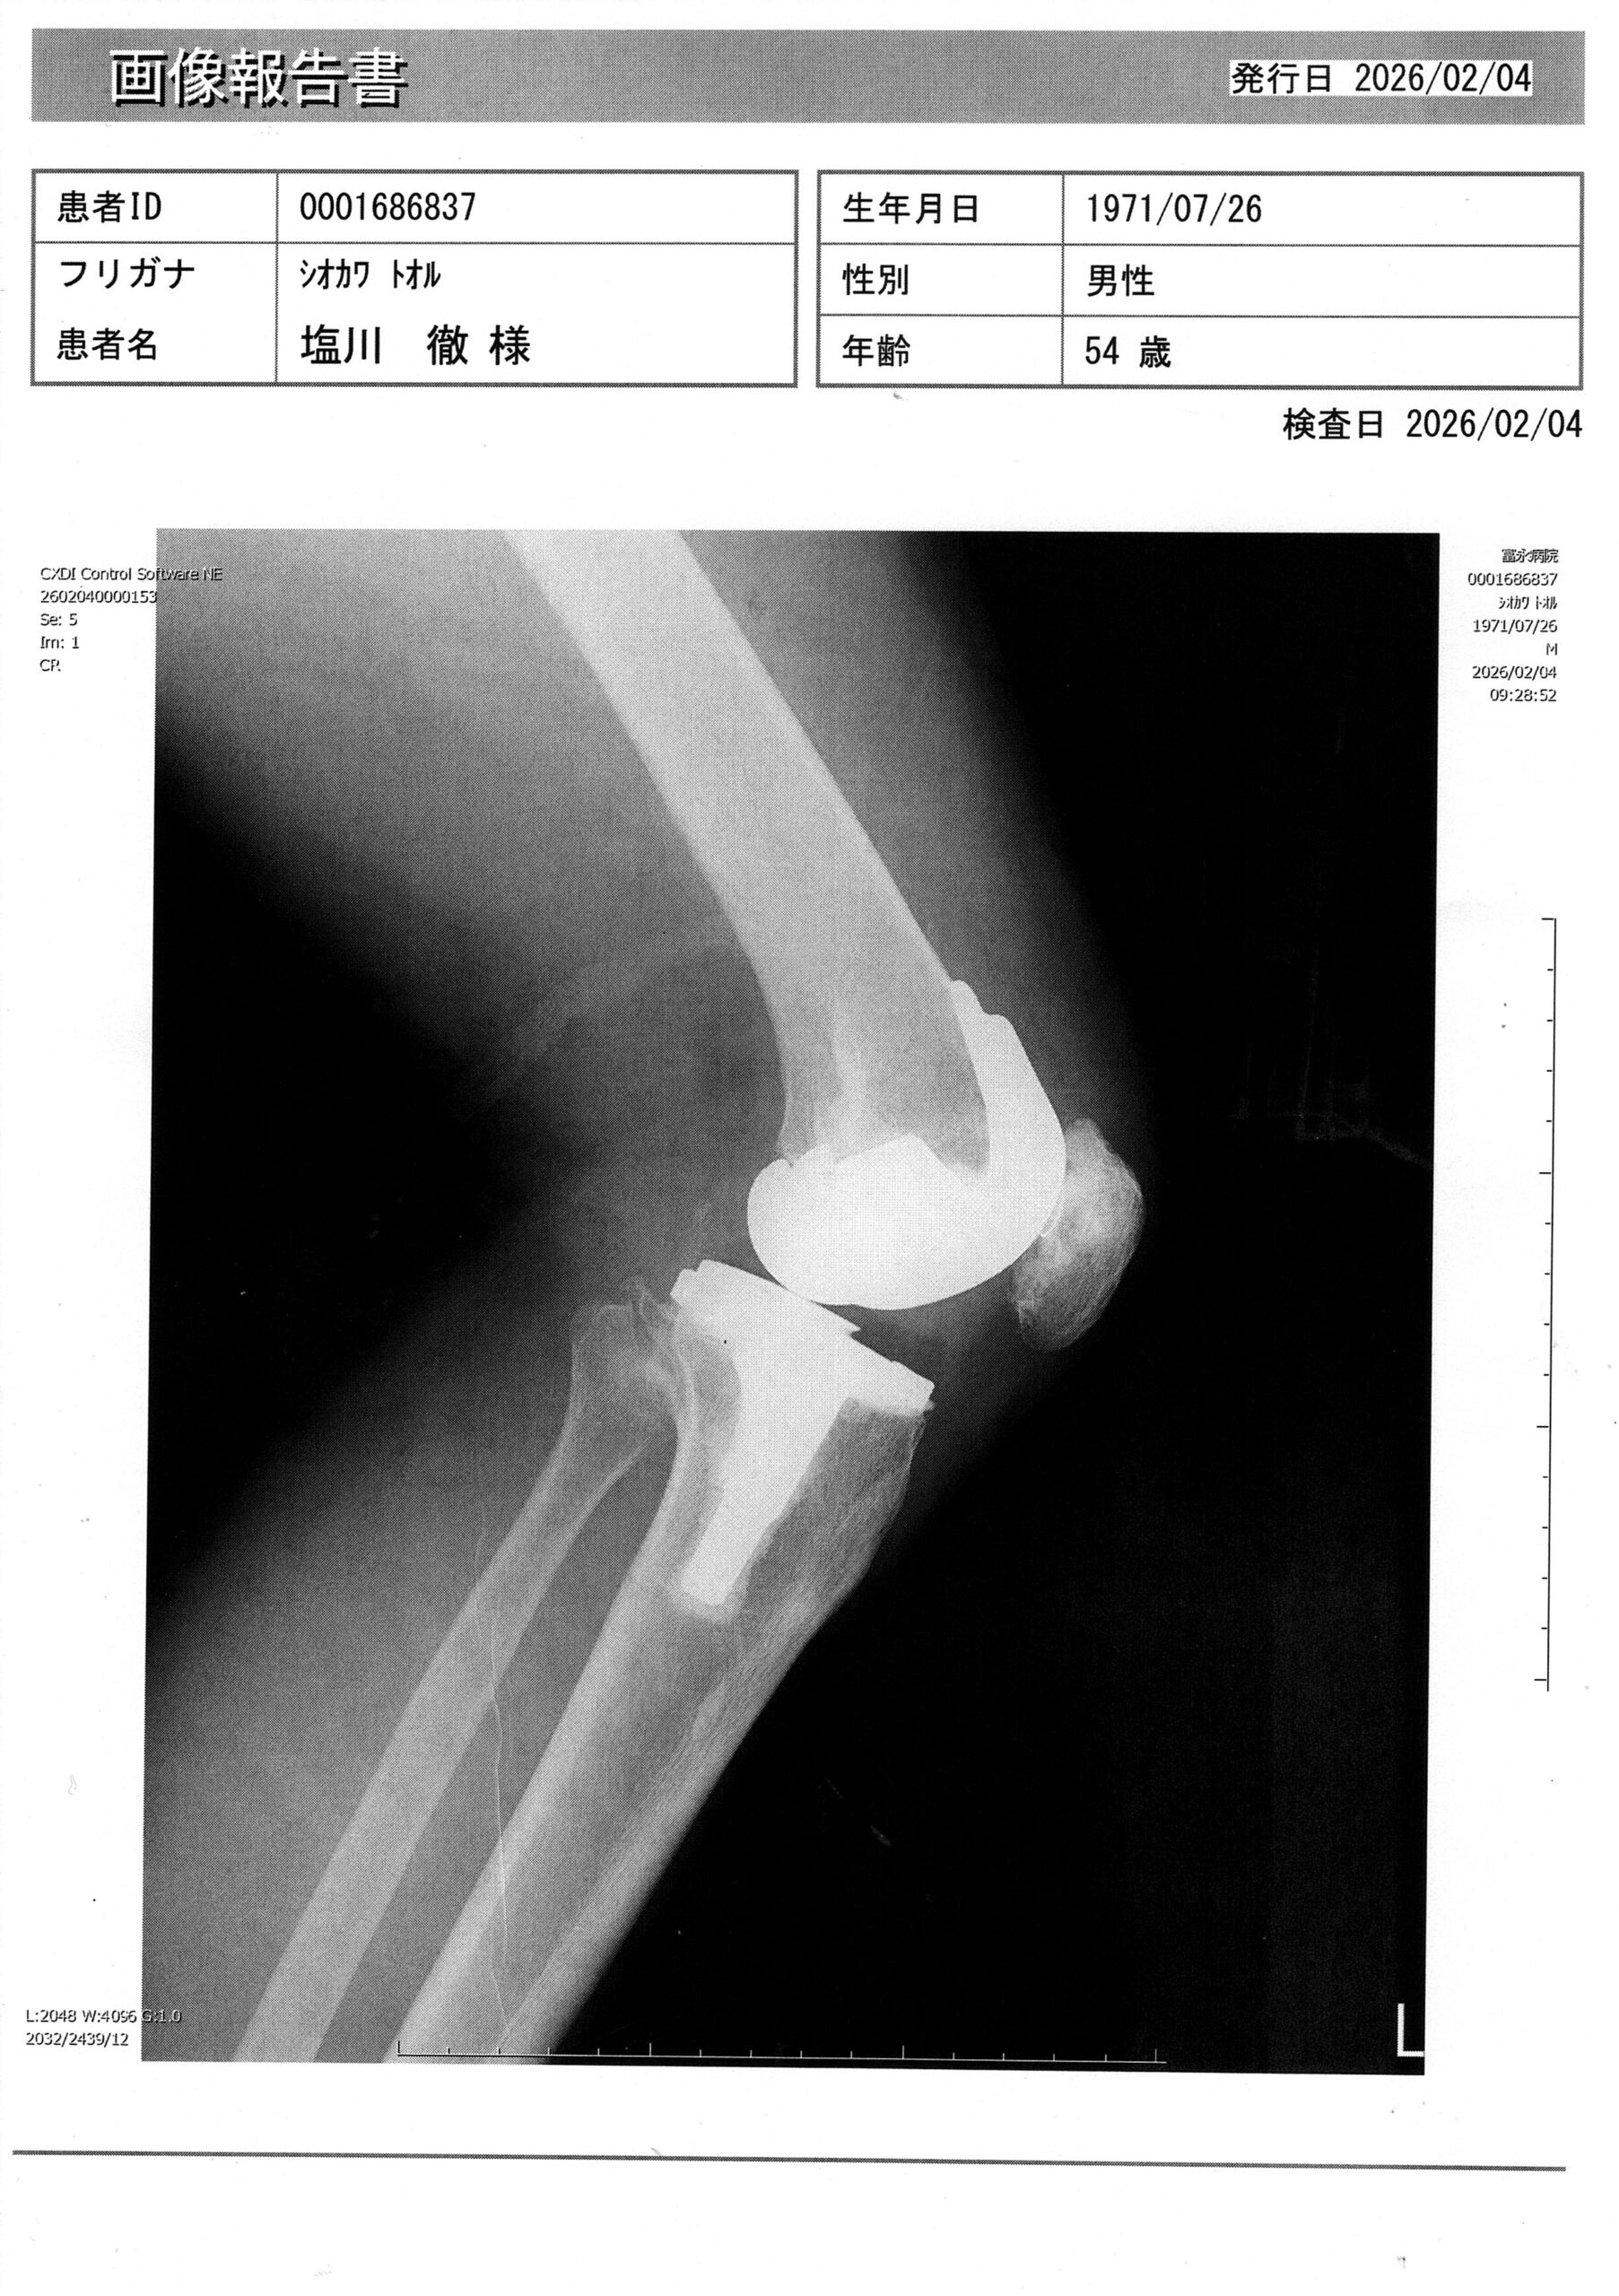

僕の左の股関節と膝関節は人工関節です。

2022年の8月に股関節を人工関節にする手術を受けまして、

2022年12月末に膝を人工関節にする手術を受けましたので、もう3年以上経つんですねぇ~

先生に、膝の曲がり具合を見せると、

「すごい! そんなに曲がるんですね! よく自力でそこまでされましたね~」

と、びっくりしながら褒めて頂きました。

自分で感じる症状的にも、普段の生活ではほぼ忘れていることが多いくらい順調です。(膝を床につくのは、縫ったところが痛くて無理で、たまにガクっと膝が崩れそうになる瞬間はありますが、、、)